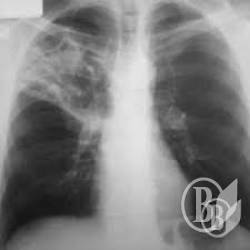

Хворих на туберкульоз залишили без ліків

ЧИТАЙТЕ ТАКОЖ: Вразливі категорії населення перевірили на туберкульоз